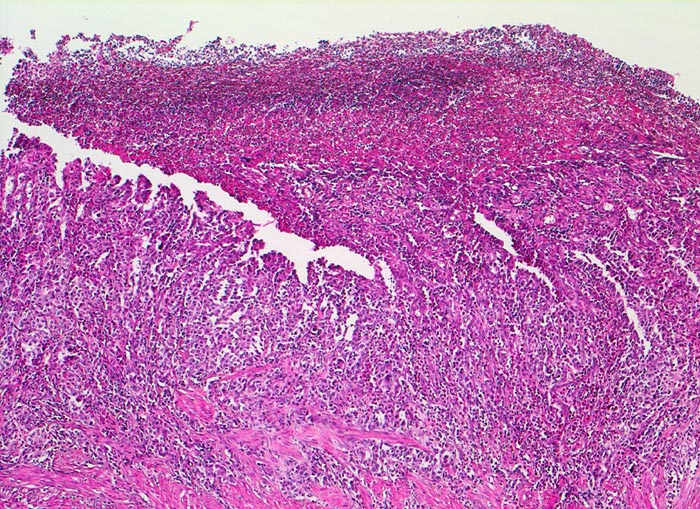

Magenfrühkarzinom

Magenantrum

Das Karzinom zeigt in diesem Abschnitt eine geringe Differenzierung. Eindeutige Drüsenbildung ist hier nicht sichtbar. Eine fibrinoleukozytäre Membran bedeckt den oberflächlich erodierten Tumor.

Endoskopische Kontrolle bei Patient mit bekannter chronischer Gastritis.

50